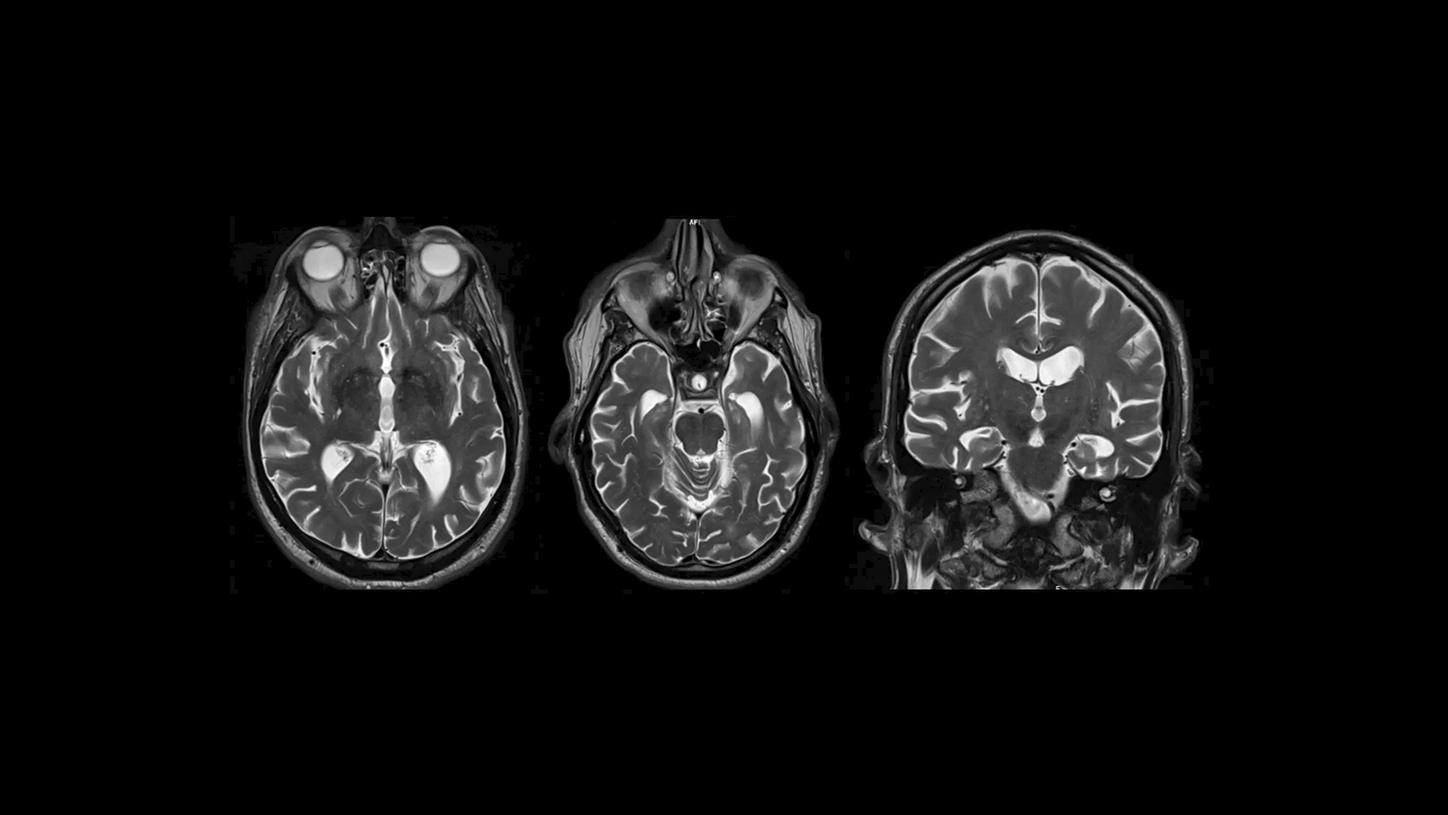

In der T2-MR-Bildgebung erscheinen Wasser und Liquor aufgrund ihrer hohen Signalintensität als helle Bereiche.

PET/MR-Bild eines Patienten mit Alzheimer.2